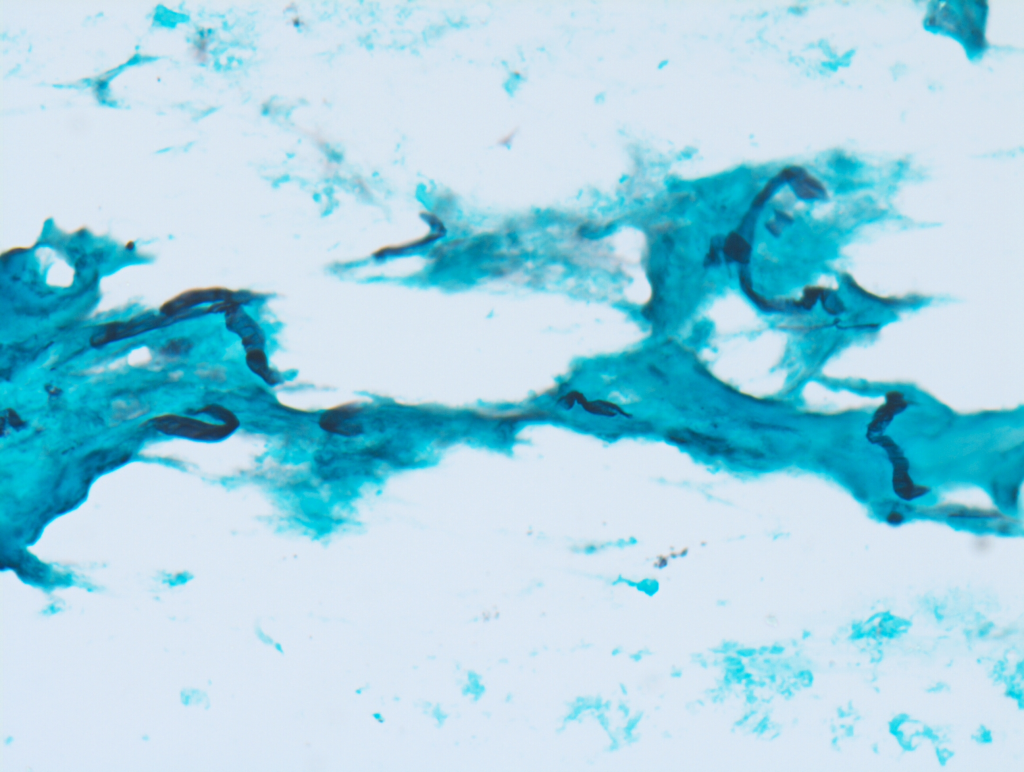

Generally, Pythium insidiosum is resistant to conventional antifungals (azoles, amphotericin B, natamycin) because it lacks ergosterol in its cell membrane. This is the key reason why patients often worsen under standard fungal keratitis therapy.

Zoospores are motile, flagellated spores produced by Pythium insidiosum. They are the infective stage responsible for corneal infection, especially in patients exposed to contaminated water or soil. Zoospores encyst, adhere to the corneal surface, and germinate, causing tissue invasion.